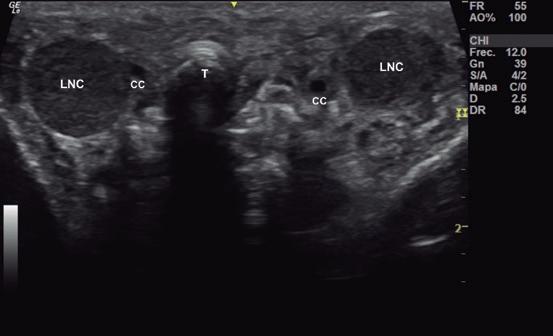

Issuu converts static files into: digital portfolios, online yearbooks, online catalogs, digital photo albums and more. Sign up and create your flipbook.